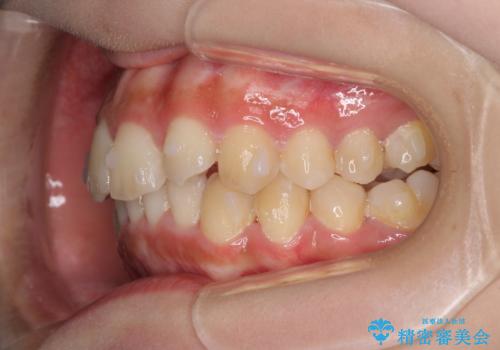

前歯のガタガタを目立たない装置でなおしたい インビザラインによる目立たない矯正

- 目立たない装置でガタガタをきれいにしたいとのご希望で来院されました。

インビザラインで矯正することとなりました。

左上の前から2番目の歯が通常とは異なる形態をしており、左右対称にすることはできませんでしたが、インビザラインで周りに気づかれることなく矯正治療をおえることができ、満足していただけました。